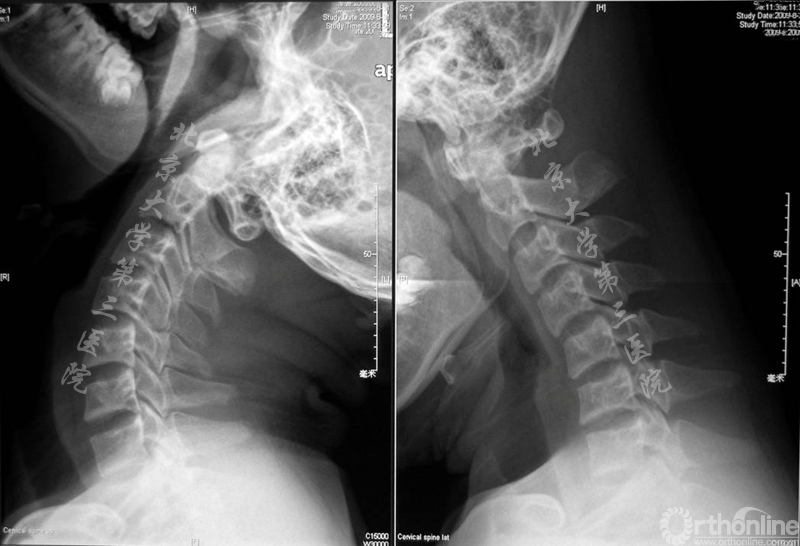

平山病患者的影像学特点为颈部屈伸活动明显增大(图2),中立位核磁脊髓无明显受压,但屈颈位MRI可见下段颈髓前移,颈脊髓在屈颈位时受到挤压(图3)。

图3.中立位核磁和屈曲位核磁,屈颈位MRI可见下段颈髓前移,颈脊髓在屈颈位时受到挤压